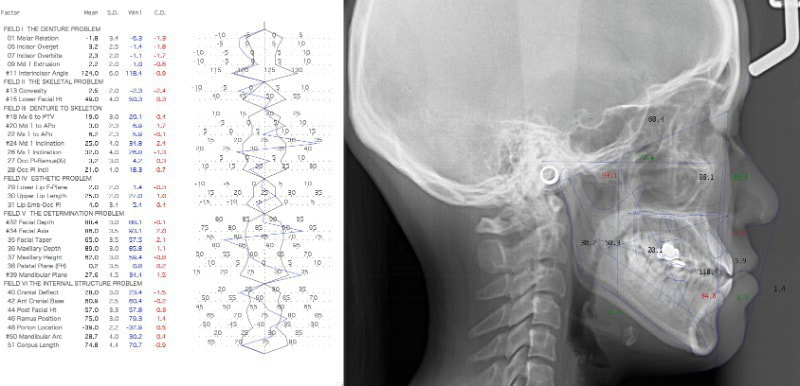

検査時のセファロ分析側貌

上顎劣成長の反対咬合の値が出ています。

検査時セファロ分析正貌

顔面の骨格的な左右非対称が認められます。